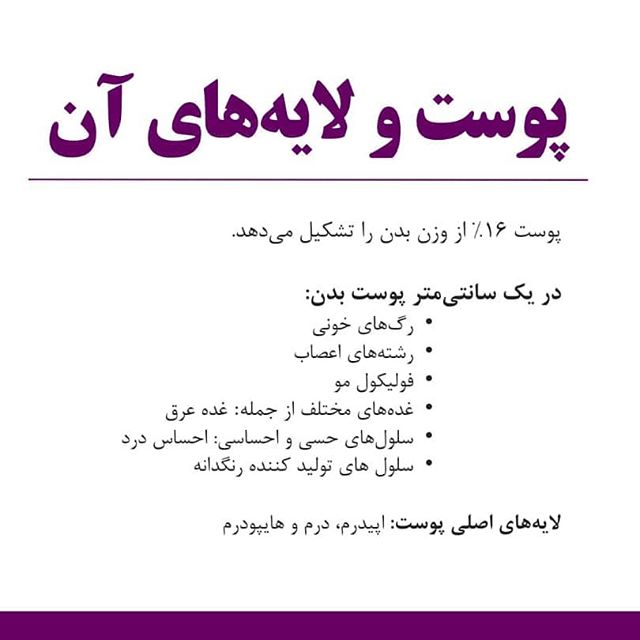

4- سطح بدن آدمی را ................پوشانده است.

6- دربخش ................پوست ، گیرنده های حسی وغدد عرق وچربی وجود دارد.

سطح بدن آدمی را پوست پوشانده است.

دربخش درونی پوست ،گیرنده های حسی وغدد عرق وچربی وجوددارد.

سلول های مرده دربخش سطحی پوست قراردارند.

پوست اولین سددفاعی بدن دربرابرمیکروب ها،سرماوگرما است.